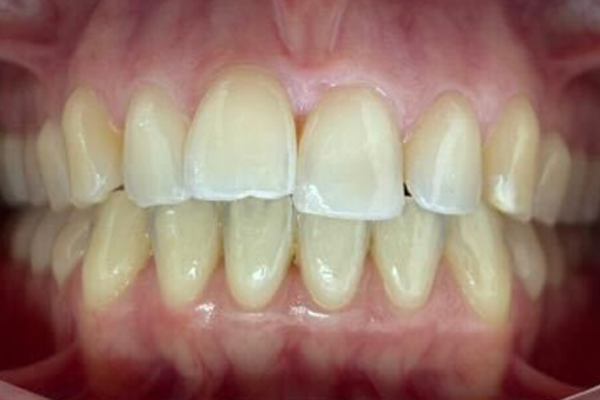

Conoce el antes y después de nuestros tratamientos